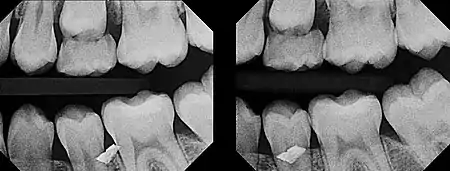

The initial radiograph (left) indicated that a metal foreign object was embedded somewhere in or near the teeth, but upon clinical examination, it could not be found anywhere in the gum tissue. Upon taking another radiograph (right) exposed at a very severe distal angulation, however, the metal fragment appeared to move a great deal to superimpose on the facial aspect of the premolar, indicating that the fragment was way more buccal than initially suspected. With the use of this second film, it was determined that the metal fragment was indeed embedded in the cheek.

Diagrammatic representation of the buccal object rule being employed. In the first radiograph (left), the objects appear on the film in almost the same relationship that they share in reality. But by shifting the x-ray collimator (radiation source) to one side and tilting it towards the objects (right), the objects appear on the film in a distorted relationship. The object closer to the x-ray collimator (generally the buccal object) will appear to reposition itself on the film at a greater distance than the object farther from the collimator (generally the lingual object) and it will appear to shift on the film in the direction of the beam.